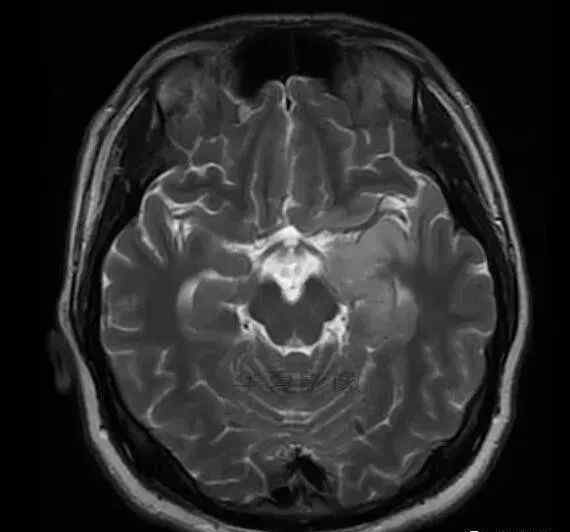

男,25岁,6天前意外感冒,现在发烧。他的体温超过39.0℃,他的呕吐物不是喷射状的。他的呕吐物是胃里的东西。

1.左侧颞叶、海马和岛叶T1WI信号低,T2WI信号高

2.病变没有明显的边界

3.占用效果不明显

4.豆状核不受影响